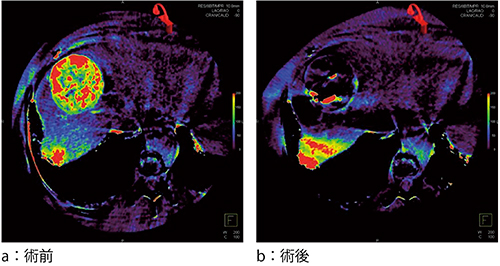

このDynaPBV Bodyを術前・術後に撮影することで,図5のように栄養血管を塞栓した腫瘍に対する血液の灌流状態を把握し,追加塞栓の要否,つまりは治療のエンドポイントの見極めとして活用することができる2)。

図5 DynaPBV Body

(参考文献2)より引用転載)